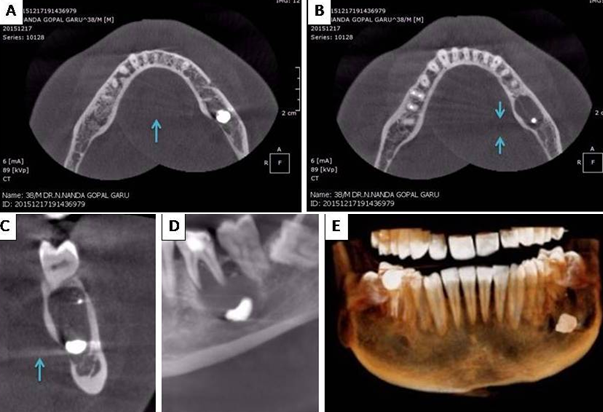

A 38 year old male doctor presented to a radiology center for cone beam computed tomography (CBCT) and the working maxillofacial radiologist spotted a very peculiar finding - There was a large piece of metal in the mandible (size 0.5 cm X 0.5 cm). Unfortunately this patient couldn’t be followed up and the reason for referral is not known. Here in we would like to provide a commentary on CBCT artifacts seen in this case along with an explanation for his case. Based on our observation the object in the mandible is certainly a metallic filling (See figure). This finding is based on the artifacts (acquisition artifacts) that were produced around the suspected material. Two types of artifacts were seen: 1. Scatter and 2.Beam hardening artifacts. Scatter occurs due to the diffraction of original beam after interaction with material. Scatter causes streak artefacts in the reconstruction (Blue arrows in panel A and C). Beam hardening artifacts were also found; they are more common. The lower energy rays suffer significant absorption when passing through the object. Higher the density and atomic number (metals) greater is the absorption. In the reconstruction image they are seen as darks streaks (Between blue arrows in panel B). Materials that often cause beam hardening include metallic restorations and titanium implants? Yes, even light metals such as titanium cause massive beam hardening and amalgam which is the material suspected in this case causes even greater hardening of beam. We strongly think that the metal must be amalgam. Some metal must have got displaced during the stage of condensation of filling in the tooth (most likely 36) just above the large radiolucent lesion. This is the most probable explanation.